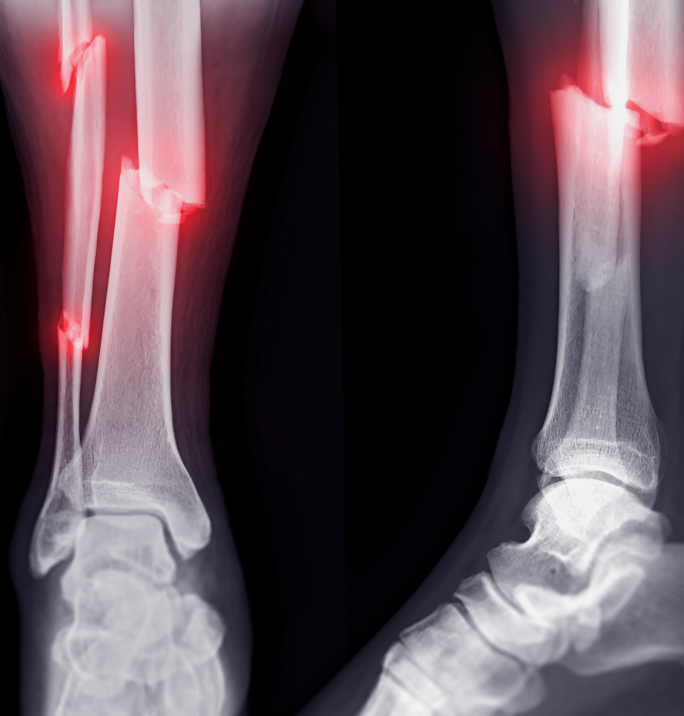

A+ 3D 골든타임 골절 수술

골절 치료의 골든 타임 72시간

놓치면 불유합부터 사망까지 초래

BEFORE AFTER

Before & After